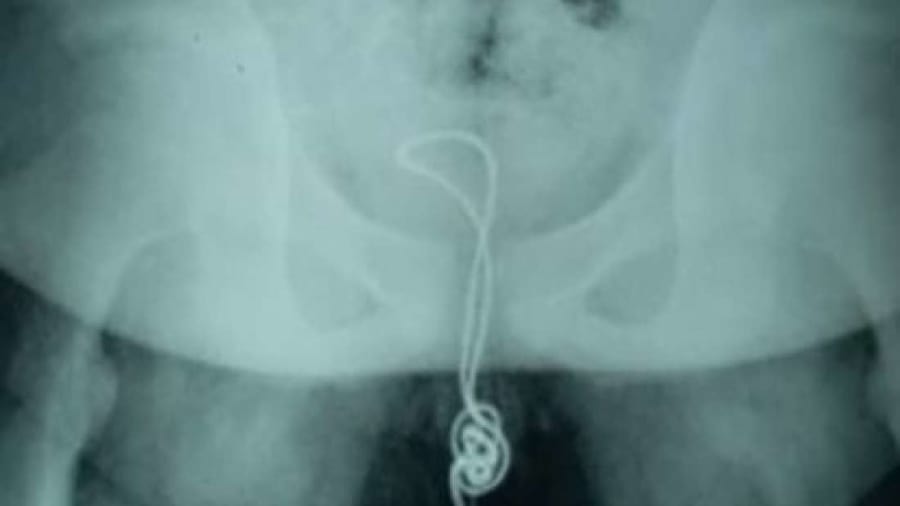

পরীক্ষার পর জানা যায়, তারটি ওই কিশোরের মূত্রথলির ভেতরে গিয়ে পেঁচিয়ে যায় এবং গিঁট লেগে যায়, এ কারণে টেনে তা বের করা যাচ্ছিল না।

পরিস্থিতির জটিলতা বুঝতে পেরে চিকিৎসকরা অস্ত্রোপচার করেন। তারা মূত্রথলি কেটে এর ভেতর থেকে তারের গিঁট লাগা অংশটি অপসারণ করেন। বাকি অংশটি তার মূত্রনালি দিয়েই বের করে আনা হয়। দুই সপ্তাহ হাসপাতালে থাকার পর বাড়ি ফিরে যায় কিশোরটি।